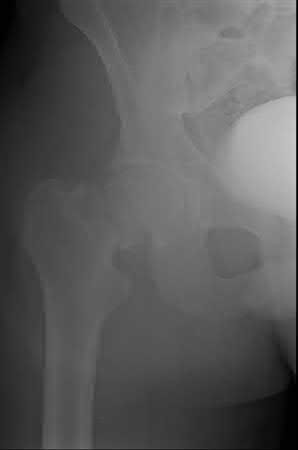

A 35 year-old female presents after prolonged extrication from a motor vehicle collision complaining of severe pelvic pain. Physical examination reveals diminished perianal sensation. She is otherwise neurologically intact. Figures A through D are radiographs and representative CT cuts of her injury. Which of the following nerve roots has likely been injured by the acute trauma?

The clinical scenario is consistent with a high-energy sacral fracture. The radiographs in figures A and B demonstrate a sacral fracture with posterior displacement of the right hemipelvis seen on the inlet view. Figures C and D are axial and sagittal CT images which show a displaced fracture of the right

hemisacrum along with a transvere fracture component through the S3 body . Diminished perianal sensation is concerning for an S2 nerve root injury.

Mehta et al reviewed the current management of sacral fractures. They note that the S1 and S2 nerve roots are more likely to be injured with sacral fractures as they occupy 1/3 to 1/4 of the neural foramina, as opposed to S3 and S4, which only occupy 1/6 of the neural foramina.

Robles reviewed the current literature to ascertain principles of evaluation and treatment for transverse sacral fractures. The author notes that injury to nerve roots S2 to S5 is manifested by impairment of urinary and anal continence and sexual function.